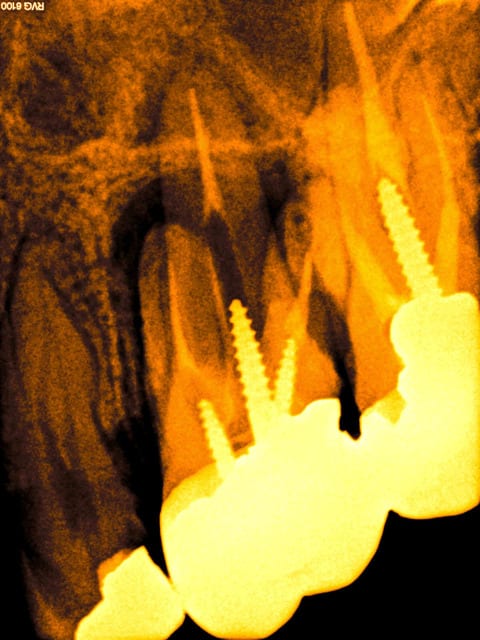

Par exemple : là j'en ai marre je vire 3 scew posts à déposer et RTE à 2 balles avec une pèche bien avancée, la merde.

1 ob5z3c - Eugenol